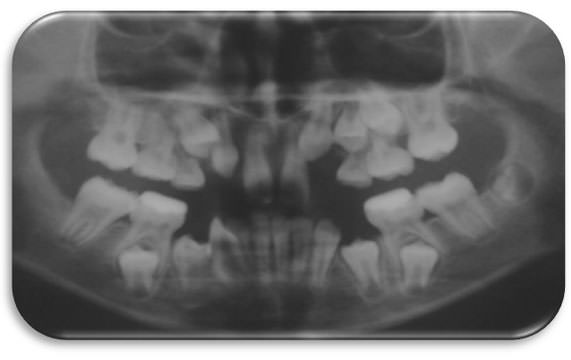

Al examen radiográfico se observa oligodoncias de 10 gérmenes dentarios, así como erupción ectópica mesial del 26. Retardo de erupción de 35 y 45. (Ilustración 4, 5, 6) En la radiografía cefálica Lateral observamos que la paciente presenta una maoloclusión Clase III esquelética, patrón de crecimiento dolicofacial, perfil óseo recto, retrusión de incisivos superiores y tejidos blandos poco armónicos. (Ilustración 7, 8)

Imagen Nº 4

Radiografía panorámica inicial. Nótese ologodoncias de 10 gérmenes dentarios, erupción ectópica mesial del 26 y áreas apicales medias y anteriores superiores comprimidas